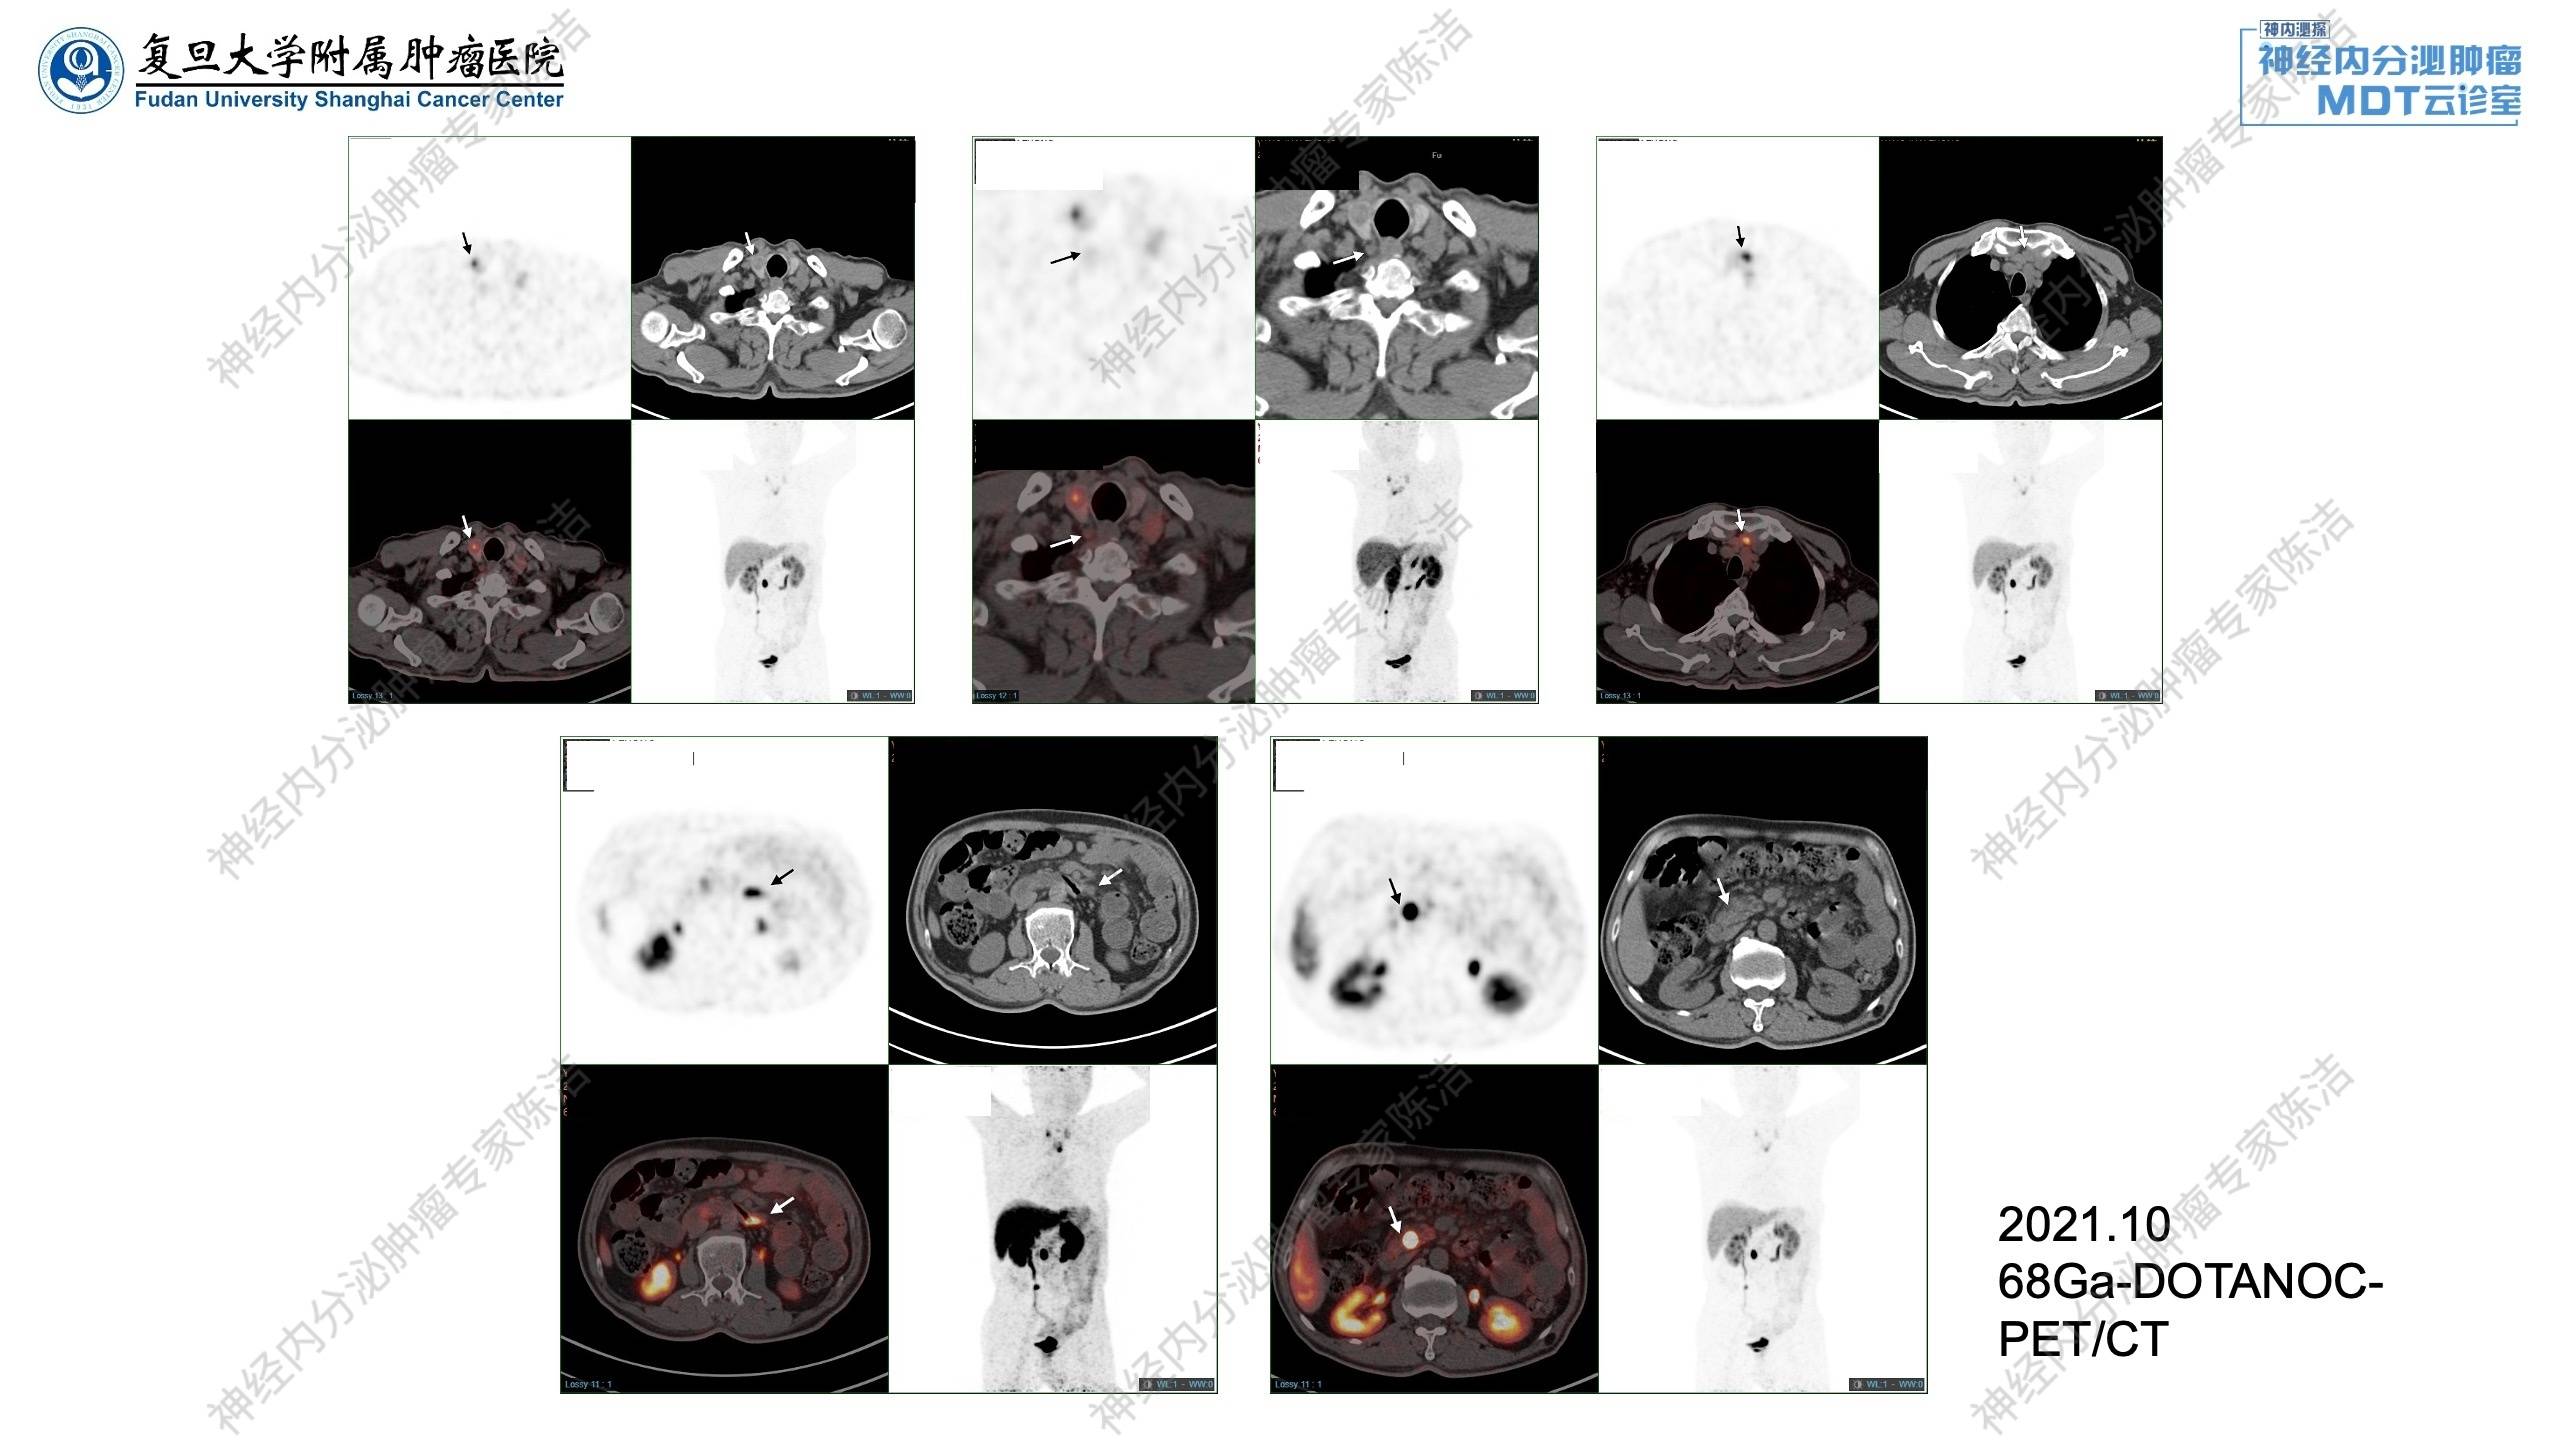

68Ga-DOTANOC-PET/CT提示胰腺神经内分泌瘤术后,胰头钩突部局灶性NOC摄取增高,考虑为神经内分泌瘤可能大;生长抑素受体高表达。左锁骨上、纵隔多发淋巴结转移,部分生长抑素受体表达轻度增高。甲状腺右叶低密度灶,NOC摄取增高;空肠起始段旁结节状NOC摄取增高灶。甲状腺右叶后方结节,未见NOC摄取增高,结合MIBI显像,考虑甲状腺旁腺腺瘤可能。

核医学科徐俊彦教授:该患者最初进行的是99mTc-TOC扫描,虽然分辨率有限,但仍显示了胰腺残端及纵隔淋巴结的SSTR高表达。随后进行的68Ga-DOTANOC-PET/CT提供了更清晰的图像,不仅确认了SSTR的高表达,还发现了更多微小病灶。